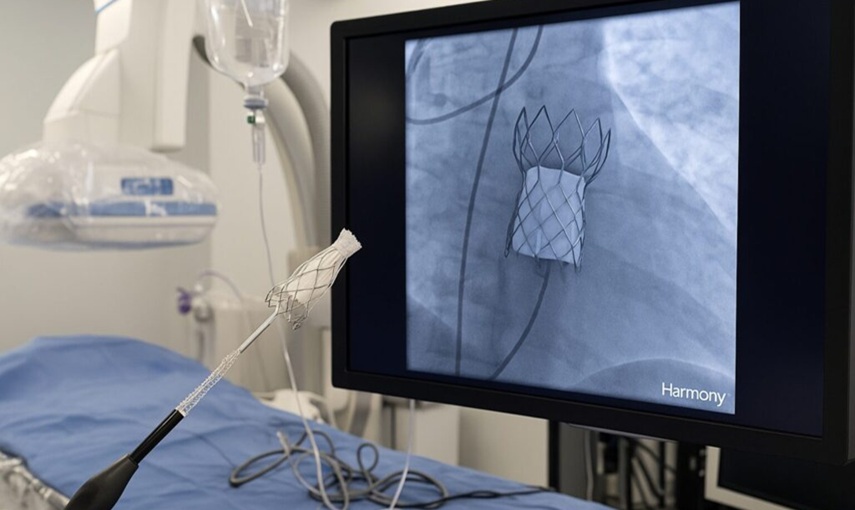

Hanno preso il via in Italia i primi impianti del sistema Harmony™ Transcatheter Pulmonary Valve (TPV), una tecnologia innovativa sviluppata da Medtronic, azienda leader di Healthcare Technology, che offre una soluzione alternativa alla chirurgia a cuore aperto per i pazienti con cardiopatie congenite.

Il sistema Harmony™ rappresenta una svolta clinica per centinaia di pazienti che, fino ad oggi, erano destinati a interventi multipli a cuore aperto nel corso della vita e consente ai medici di trattarli in modo più sicuro ed efficace, migliorando la loro qualità della vita.

Il dispositivo, già impiantato con successo in oltre 2.800 pazienti a livello internazionale, è ora disponibile anche in Italia in cinque centri ospedalieri di riferimento per la cardiologia pediatrica e congenita: Ospedale Pediatrico Bambino Gesù di Roma; Azienda Ospedale-Università di Padova; Policlinico Sant’Orsola-Malpighi di Bologna; IRCCS Policlinico San Donato e Ospedale Papa Giovanni XXIII di Bergamo.

Harmony™ TPV è progettata per offrire una valida alternativa all’intervento chirurgico tradizionale di sostituzione della valvola polmonare. La procedura di impianto avviene infatti tramite un sistema transcatetere e consente un recupero più rapido e minori rischi operatori.

I dati clinici a tre anni confermano risultati eccellenti in termini di funzionalità valvolare, adattabilità anatomica, sicurezza e durata dell’efficacia.